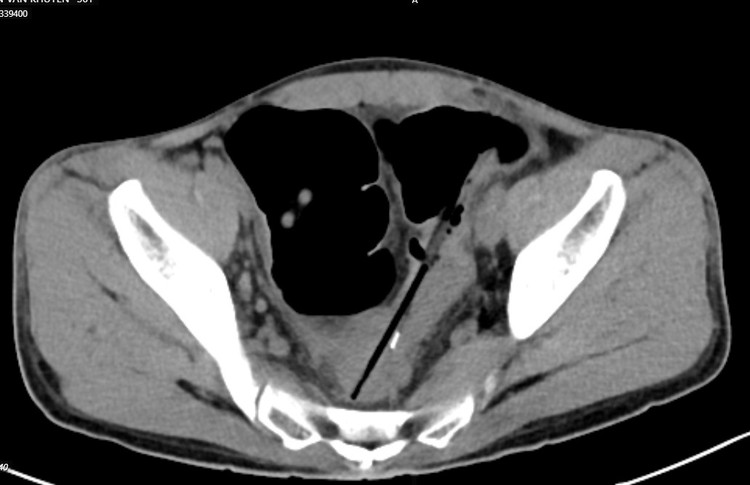

Chụp cắt lớp ổ bụng thấy hình ảnh 02 dị vật hình que đầu kim loại trong quai ruột vùng hạ vị, đâm xuyên thành ruột tạo ổ dịch khí vùng tiểu khung cạnh cơ bịt phải; Dị vật trong quai ruột hạ sườn phải; Dày thành trực tràng, đại tràng sigma và quai ruột ngang rốn; Giãn lan tỏa các quai ruột non.

| Bệnh nhân được chẩn đoán: Áp xe trong ổ bụng do thủng đại tràng sigma do dị vật, dị vật ruột non/tâm thần phân liệt. |